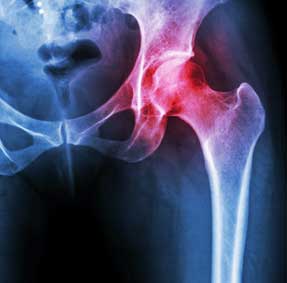

Mako is a technique used by surgeons for partial knee resurfacing, total knee replacement and total hip replacement. It is an innovative treatment option for adults living with early to mid-stage joint degeneration of the hip or knee.

Eligibility

Mako is an option for adults living with early to mid-state osteoarthritis in the knee and hip, or people who suffer from degenerative joint disease. Talk to one of our orthopedic surgeons to see if Mako is an option for you.